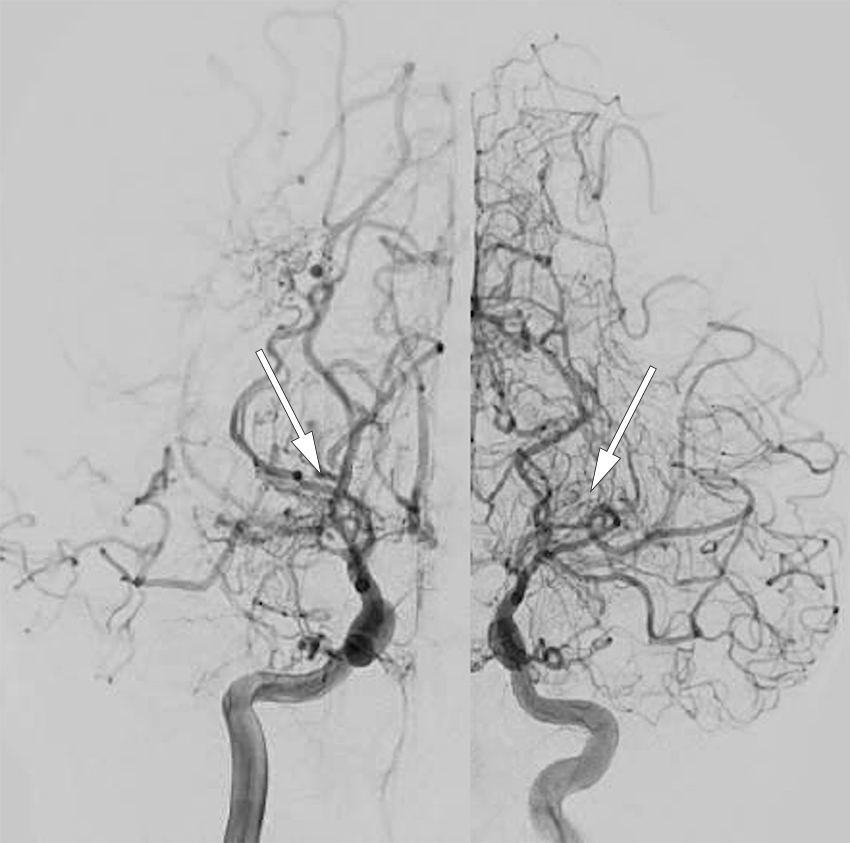

Konvensjonell cerebral angiografi med fremstilling av både a. carotis interna, a. carotis externa og a. vertebralis er fortsatt gullstandarden i diagnostikk av moyamoya (figur 1). En slik invasiv undersøkelse hos barn innebærer en viss risiko, og derfor anbefales primært MR med MR-angiografi ved diagnostikk av moyamoya hos barn, mens konvensjonell cerebral angiografi utføres først i forbindelse med planlegging av en eventuell operasjon.

Ofte brukt er Suzukis angiografiske gradering av moyamoya i seks stadier (2), som gjenspeiler alvorligheten i det kliniske forløpet. Vår erfaring er at den radiologiske presentasjonen av moyamoya hos norske pasienter av ikke-asiatisk opprinnelse kan avvike noe fra det klassiske bildet, hvilket kan forsinke og gjøre det vanskeligere å stille riktig diagnose (12).